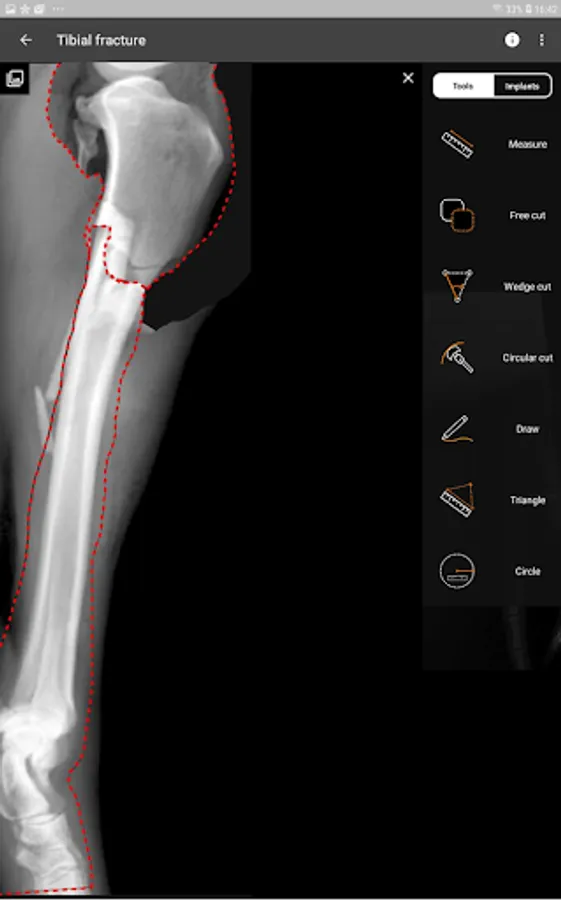

3. Tools:

a) Linear Measure.

b) Radial measure/Circle draw.

c) Angle measure/Triangle draw.

d) Free cut.

e) Wedge cut, CTWO and angular osteotomies.

f) Circular cut, TPLO.

g) Free Draw.